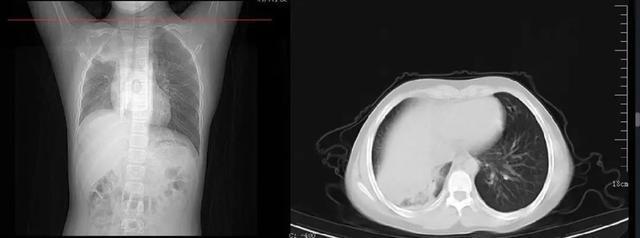

白肺

一般情况下,转阴后伴有咳嗽是正常的,可能会持续一到两周。 但是,如果患者有明显的咳嗽、咳痰、发热,而且病情在逐渐进展,尤其是出现胸闷、气短等症状,就应该及时到医院就诊。 这时阳康后咳嗽怎么办,可能会出现“白肺”。